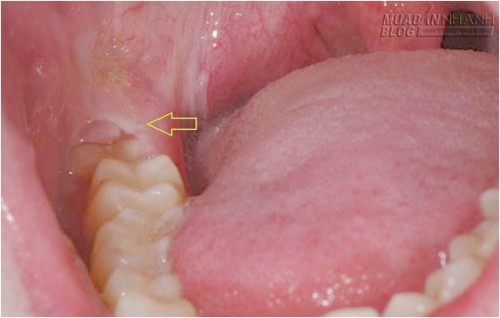

Do mọc sau cùng nên răng khôn hàm dưới có thể bị thiếu chỗ để mọc một cách bình thường, dẫn đến mọc lệch, mọc ngầm. Những trường hợp này gọi chung là mọc kẹt, nghĩa là cái răng đó không có đủ chỗ để mọc lên bình thường hoặc hướng mọc bị nghiêng nên không trồi lên được.

Khi răng khôn hàm dưới mọc ngầm, có thể sẽ có nang thân răng bao quanh và gây viêm nhiễm. Răng khôn mọc lệch sẽ dễ gây kẹt thức ăn và khó vệ sinh răng miệng, dẫn đến viêm nhiễm. Răng khôn hàm trên nếu thiếu chỗ thường mọc chếch ra phía má và phía sau. Trong lúc ăn nhai, bệnh nhân dễ cắn phải má. Nói chung, răng khôn hàm dưới thường gây biến chứng nhiều hơn và nặng hơn hàm trên.